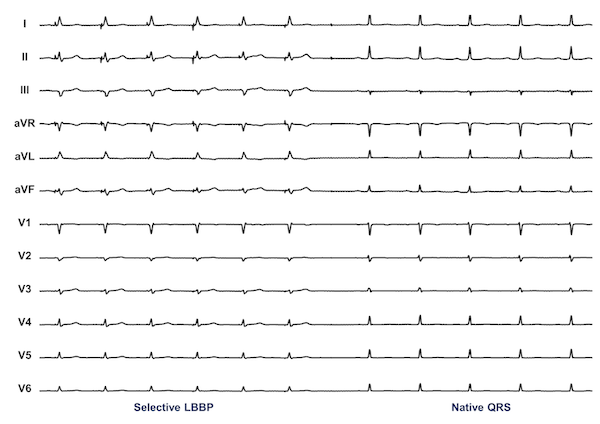

The criteria for assessing conduction system capture for patients undergoing His bundle pacing (HBP) have now been established.14 Particularly among patients with narrow QRS at baseline, the template for assessing conduction system capture is the patient’s intrinsic QRS. In patients undergoing HBP for CSP, the goal is to reproduce this QRS as closely as possible across all 12 leads of the standard surface ECG. Selective capture is present when an identical QRS or near-identical is inscribed with an isoelectric segment present between the stimulation artifact and the QRS onset in all 12 leads (Figure 1). Nonselective capture is present when there is a “pseudo-delta” or slurred upstroke beginning at the stimulation artifact in at least one lead (Figure 2). Critical in patients undergoing HBP is that output-dependent morphology (ODM) changes should be present, which allow implanters to distinguish between nonselective HBP and RV septal capture.15,16 There may be a small cohort of patients in whom ODM changes are not present with HBP, and use of pacing maneuvers may be helpful to help distinguish morphologic differences in this setting.17,18

The situation is more complex for left bundle branch pacing (LBBP), in which nonselective pacing is associated with a narrower paced QRS than selective LBBAP.19 Unlike HBP, the criteria for assessing conduction system capture for LBBP have not yet been standardized, and discriminating nonselective LBBP from left ventricular septal myocardium-only capture remains challenging (see Question 4 below).